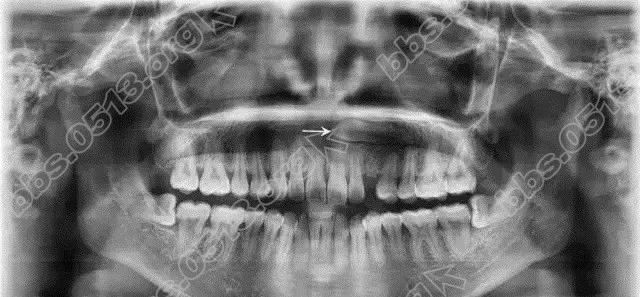

3 D% d- s% f- v- ?3 ?3 p* O2 D报名对象 针对牙齿不齐、牙齿拥挤、牙齿稀疏、龅牙的患者